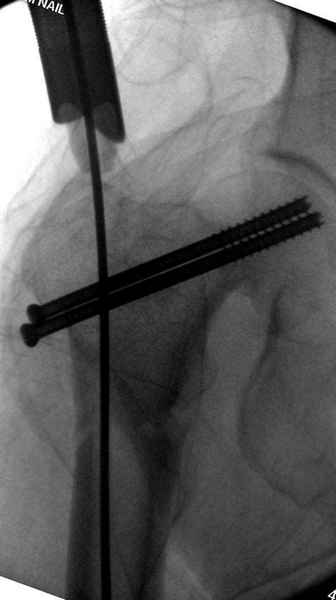

Правильно, ситуация изменилась, как говорят у нас теперь "different animal", надо решать проблему подвертельного перелома. При наличии различных вариантов фиксаторов, включая Страйкер Гамма 3, мы выбрали DePuy Antegrade Trachanteric Nail из-за многовариантности проксимальной фиксации и двойного изгиба. Вводится через вертел под 8 градусным углом, и есть достаточный передний диафизарный изгиб, предупреждающий пенетрацию дистального переднего кортекса.